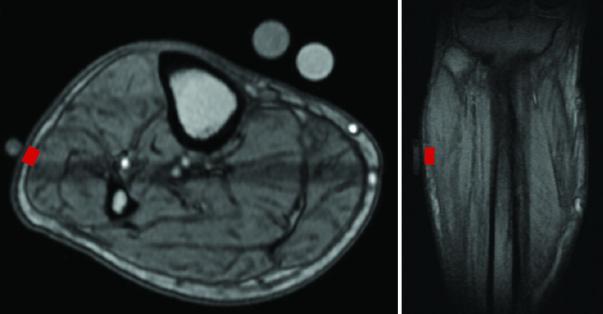

Lina Colucci and colleagues have created a portable device that within 45 seconds accurately detected excess fluid buildup in the legs of seven participants with end-stage kidney failure. Their device is based on the same technology as that of larger MRI machines, but can take measurements at a fraction of the time and cost, indicating it could help prevent complications in patients with excess fluid levels. Treating patients with fluid buildup requires striking a delicate balance; removing too little fluid leaves them at risk of hypertension and heart failure, while removing too much leads to muscle cramps and low blood pressure. Fluid buildup, which impacts over six million people in the U.S., occurs in conditions such as kidney and congestive heart failure and costs the U.S. more than $35 billion annually, but current imaging techniques such as MRI machines are expensive and can only be used in hospitals, making them impractical for routine use. Lina Colucci and colleagues created an alternative, non-imaging tool based on portable nuclear magnetic resonance (NMR) sensors, which can noninvasively assess fluids and their environment. Their platform contains a single-sided NMR sensor harboring 180 individual magnets, and was found to provide accurate measurements of leg fluid buildup when applied to seven participants with end-stage kidney disease, which were matched by results from an MRI machine and an FDA-approved device that estimates body fat and muscle mass. The authors believe their platform's portability and ease-of-use could allow clinicians to track fluid buildup at the bedside in a manner not possible with larger machines.